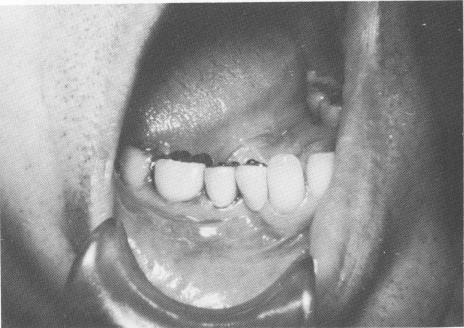

Fig. 8-58. The gold coping is picked up inside the anterior crown with cold cure acrylic.

Fig. 8-59. The two-unit splint is cemented into position with

4 Interchangeable gold coping placed over vent plant implant shaft

5 Gold coping picked up inside vent plant implant crown with acrylic

6 Two-unit lower vent plant implant splint cemented in position